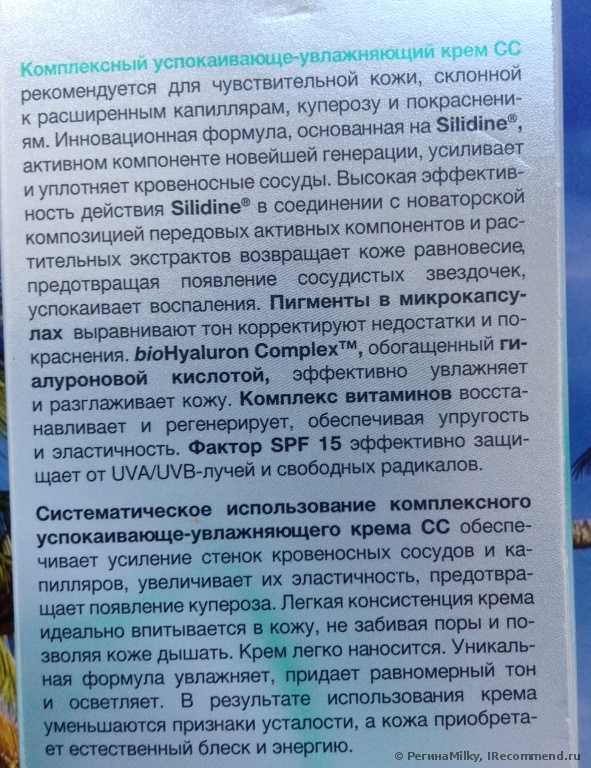

Когда мне понадобился легкий сонцезащитный крем для лица на лето, то в первую очередь я подошла к полкам с «Eeveline cosmetics», потому что это одна из любимых мной марок. Мое внимание привлек этот крем, потому что производитель обещает уменьшение купероза, увлажнение и смягчение кожи, защиту от УФА и УФБ лучей (SPF 15), коррекцию тона и мелких недостатков. Все эти обещания были кстати для летнего ухода. Крем не дорогой (142 руб), поэтому рискнула попробовать, не особо вчитываясь в состав. Дома вскрыла упаковку и познакомилась к кремом поближе.

Крем оказался нежной консистенции и бледно-зеленого цвета, с темными микро-капсулами пигментов. Зеленый тон всегда используется для маскировки покраснений. Запах легкий, травянистый, нейтрально ароматный.

При нанесении на кожу он легко распределяется без липкости или жирности. Действительно при растирании крем теряет свой зеленый оттенок и кожа приобретает цвет легкого загара (чем сильнее я растирала, тем темнее получался «загар»). Расширенные сосуды он слегка маскирует, тон кожи выравнивает. Если наносить крем специальным спонжем для тонального крема, то он ложится ровно тонким слоем, не приходится растирать и поэтому оттенок остается очень светлым, так лучше маскируются сосудики и покраснения. На лице крем не ощущается, эффекта маски нет. Не рекомендую наносить крем толстым слоем или в несколько слоёв, потому что при повторном растирании ранее нанесенного крема оттенок станет более темным. Я наношу крем один раз и хожу с ним весь день, кожа выглядит естественно, неприятных ощущений нет, вообще его не замечаю. Вокруг глаз его наносить нельзя, для этого я приобрела специальный крем для век Eveline с УФ защитой.

Одной тубы (30 мл) мне хватило почти на 2 месяца. За это время я заметила, что сосудики стали менее выраженными и краснота уменьшилась. Кожа разгладилась, уменьшились морщинки. Крем обладает матирующим эффектом и я перестала пользоваться пудрой. Правда в течении дня появляется легкий лоск, для снятия которого прикасаюсь слегка к лицу бумажной салфеткой.

Конечно для достижения более выраженного эффекта нужно больше времени, поэтому вчера купила новую упаковку крема, буду пользоваться все лето, о результатах сообщу. Крем достаточно стойкий, с минеральными пигментами, поэтому вечером убираю его мицеллярным раствором Eveline. На ночь тонким слоем наношу «Активный отбеливающий крем» Eveline. На фото видно, что в целом кожа стала светлее, пигментные пятна уменьшились. Днем пигмента не прибавляется благодаря сонцезащитным свойствам крема СС, а ночью кожа осветляется под действием отбеливающего крема.

Что касается состава, то крем действительно содержит экстракты лекарственных растений и витамины (см. в «Подробностях»), но они в самом конце списка ингредиентов, после 4 парабенов, касторового и кокосового масел), а в начале списка (первые 10 позиций) после воды значатся различные натуральные и синтетические эмоленты (вещества смягчающие и увлажняющие кожу, облегчающие распределение и нанесение крема). Поэтому одну звезду снимаю.

Это SOS крем для сосудистой кожи, склонной к появлению купероза и покраснений.

Скажу сразу, купероза у меня нет, возможна только предрасположенность, а вот покраснения постоянны, помимо пятен постакне, румянец всегда со мной.

То, что обещает производитель, мне очень понравилось, но я не особо верила. Тут же и состав.

Сам крем имеет зеленый оттенок с коричневыми микрогранулами. Если хорошо его размазать, то цвета он практически не дает.

Впитывается крем очень хорошо, не оставляет пленки и неприятных ощущений. Хорошо увлажняет и при этом матирует кожу. Эффект от крема видно сразу. Краснота проходит. Посмотрите на общий тон кожи, пятна постанке конечно он не скроет до конца, но даже они становятся светлее. И это достигается без тонального эффекта! Просто ровный цвет лица.